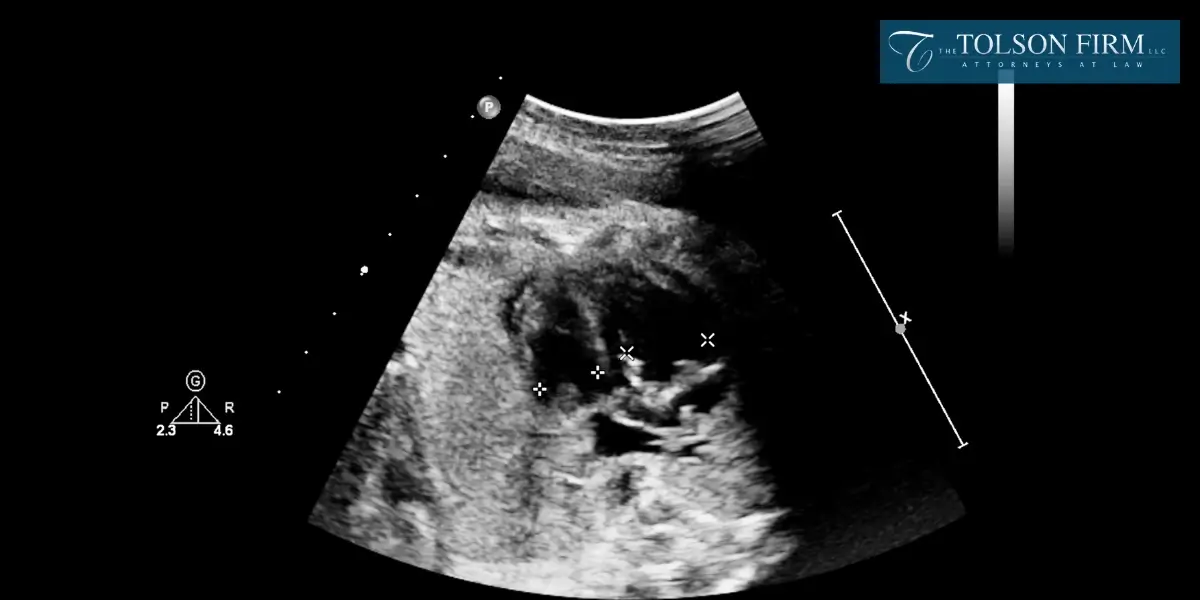

There are many kinds of evidence that can be helpful with a fetal death claim in Gainesville, Georgia. With your attorney, you may gather medical records, expert medical opinions, witness testimony, fetal monitoring data, pathology reports, communication records, hospital protocols and policies, and documentation of damages. Your attorney can help identify and present the most important evidence to support your case. With powerful evidence, it can strengthen your legal arguments and increase your odds of a favorable claim outcome.